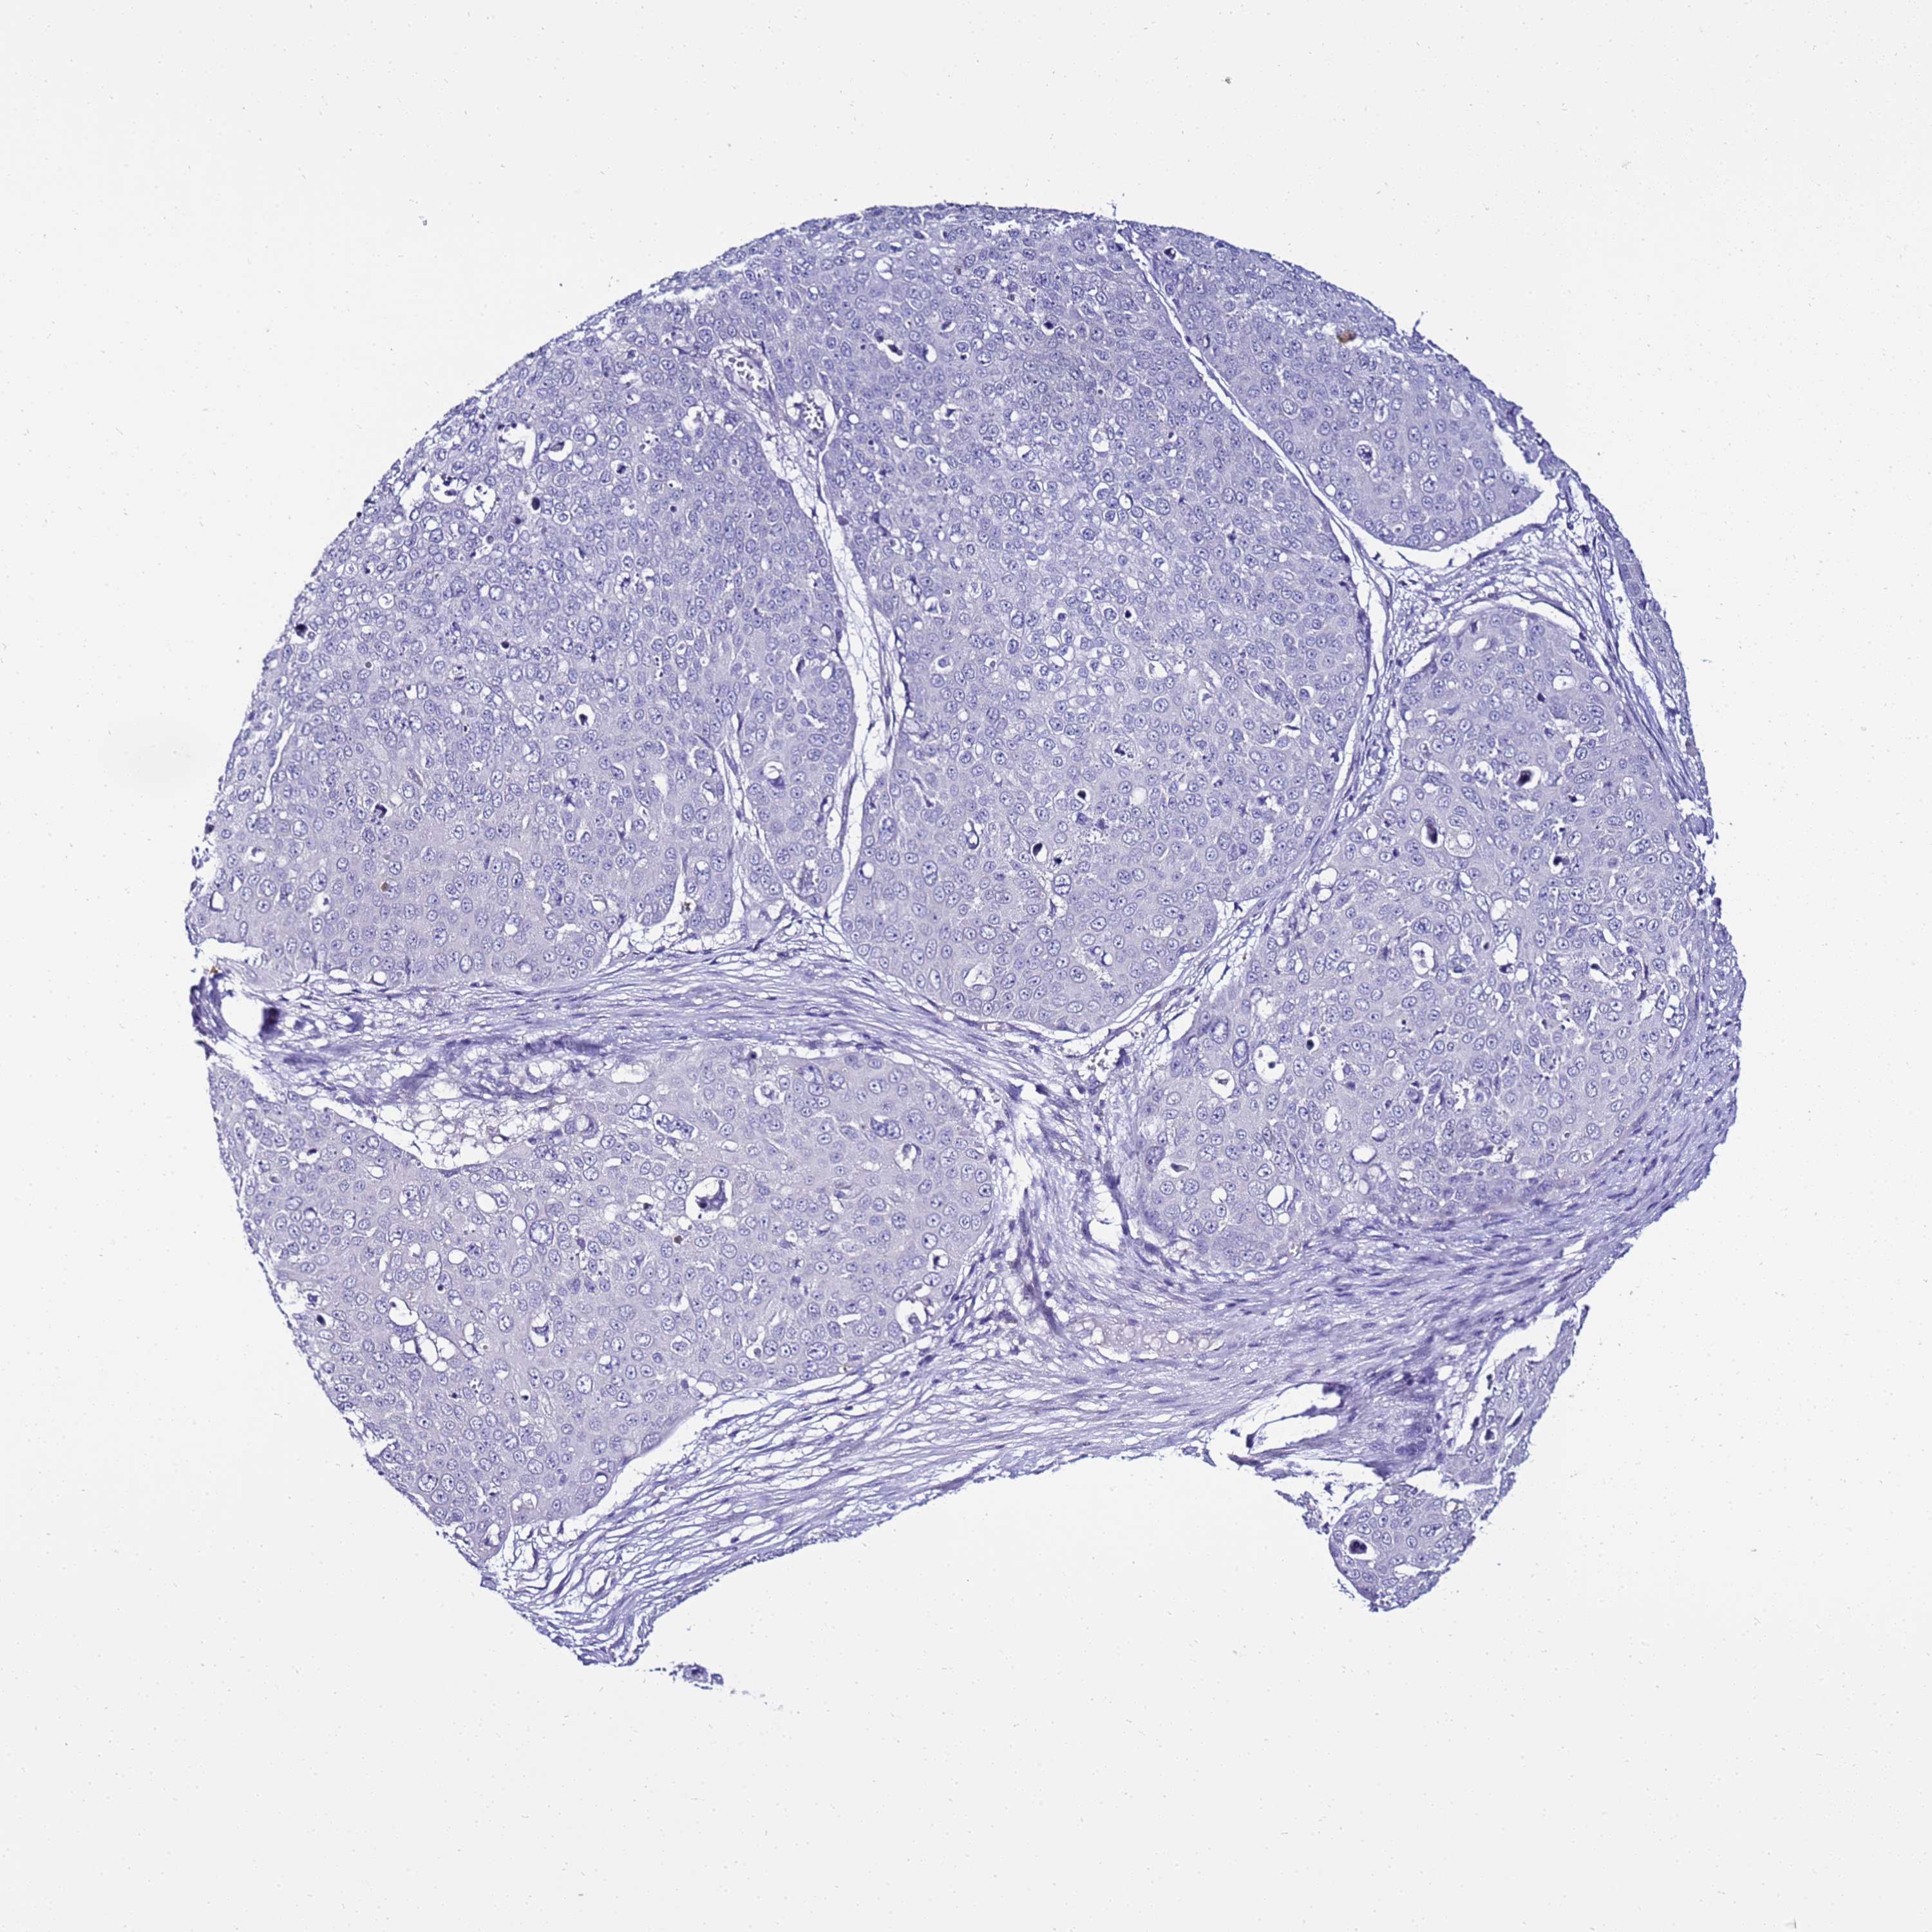

Basal cell and squamous cell cancer

SKIN CANCER - Protein expressioni

A mouse-over function shows sample information and annotation data. Click on an image to view it in a full screen mode. Samples can be filtered based on level of antibody staining by selecting one or several of the following categories: high, medium, low and not detected. The assay and annotation is described here.

Each image is clickable and will lead to virtual microscopy that enables deeper exploration of all samples and also displays staining intensity scores, fraction scores and subcellular localization as well as patient and tissue information for each sample.

Antibody HPA045540

Basal cell carcinoma